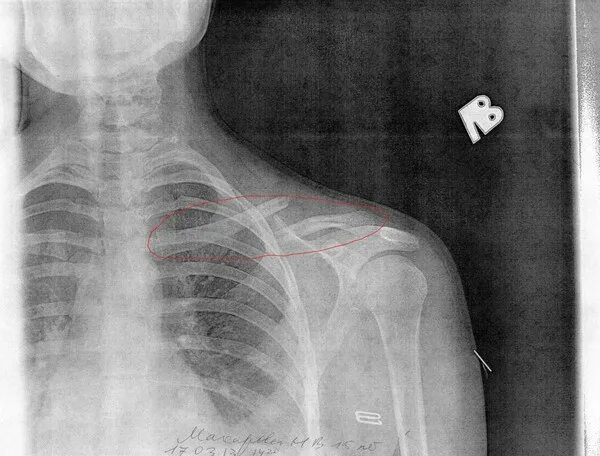

Сколько срастается ребро при переломе